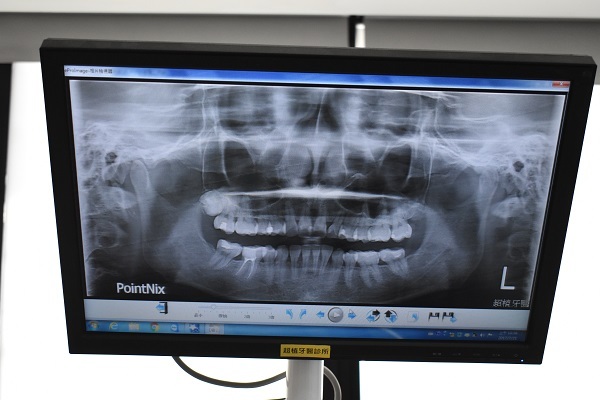

諮詢師跟我說,為確保患者在美白過程不傷及牙齦,

他們院內會先施行全口的X光口腔照攝評估,

然後做蛀牙治療檢查,補完蛀牙最快隔一個禮拜就可以進行冷光美白。

仁芬醫生跟我說我要先去做個X光掃描!

於是我在其他護士小姐引領之下我們去做全口牙齒X光評估照攝!

一方面是要了解我的牙齒狀況適不適合做美白的療程,

若有牙結石或嚴重蛀牙可能就要小心為妙了!

幸好!檢查出來我是可以做冷光美白療程!真的超開心!